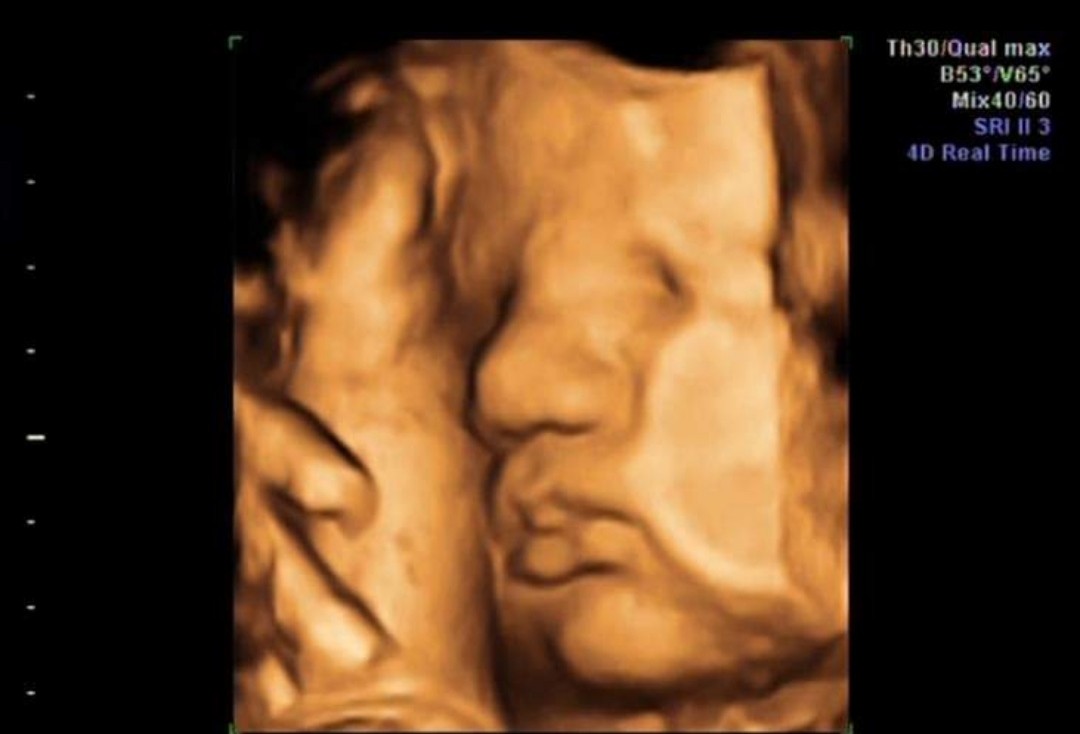

Podobno rośnie około 1 mm dziennie, więc by się zgadzałoPiękny Krasnalek